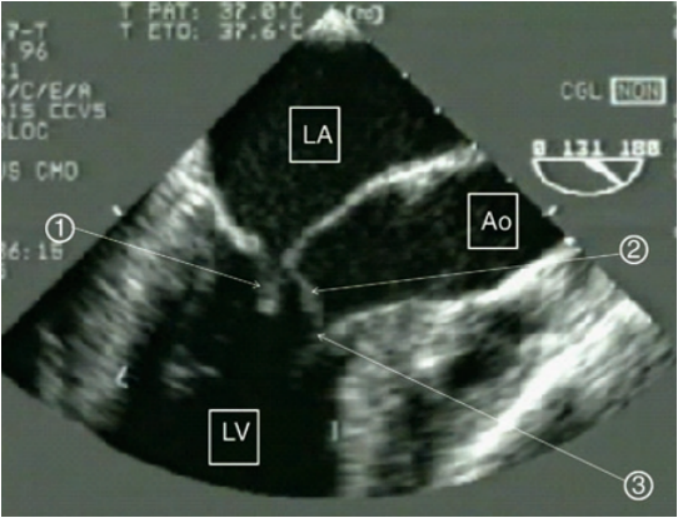

超声检测心包积液的能力取决于积液的大小和在不同超声视窗的分布,较大的积液导致心脏周围可见的无回声空间。通过长轴切面,可以检测到少量后心包积液;通过心尖四腔切面,可以评估右心房、右心室游离壁的运动(图4)

图片

4  心包积液的超声检测(*区域为心包积液)

心脏压塞的超声诊断:包括右心腔在吸气时增大的比例下降、右心房收缩期塌陷、右心室游离壁在舒张期塌陷、下腔静脉内径增宽呼吸变化率减低(视频1,图5)。右心房的收缩期塌陷是早期心脏压塞的一个敏感标志,早期阶段敏感性为50%,晚期阶段敏感性可达100%。然而,在右心室充盈压力升高的患者中,如由肺动脉高压或高血容量引起,跨膜压力可能需要更高才能导致心房塌陷,从而降低压缩效应。

此外,还有一些特殊情况,例如:外科术后出现心包内血肿、纵隔血肿,心包粘连、肿瘤,都可能导致超声图像不典型,需要经食道超声辅助(图6,图7)

6  经食道超声显示心包内巨大血肿

7  右心房被血肿压迫,血流信号减少